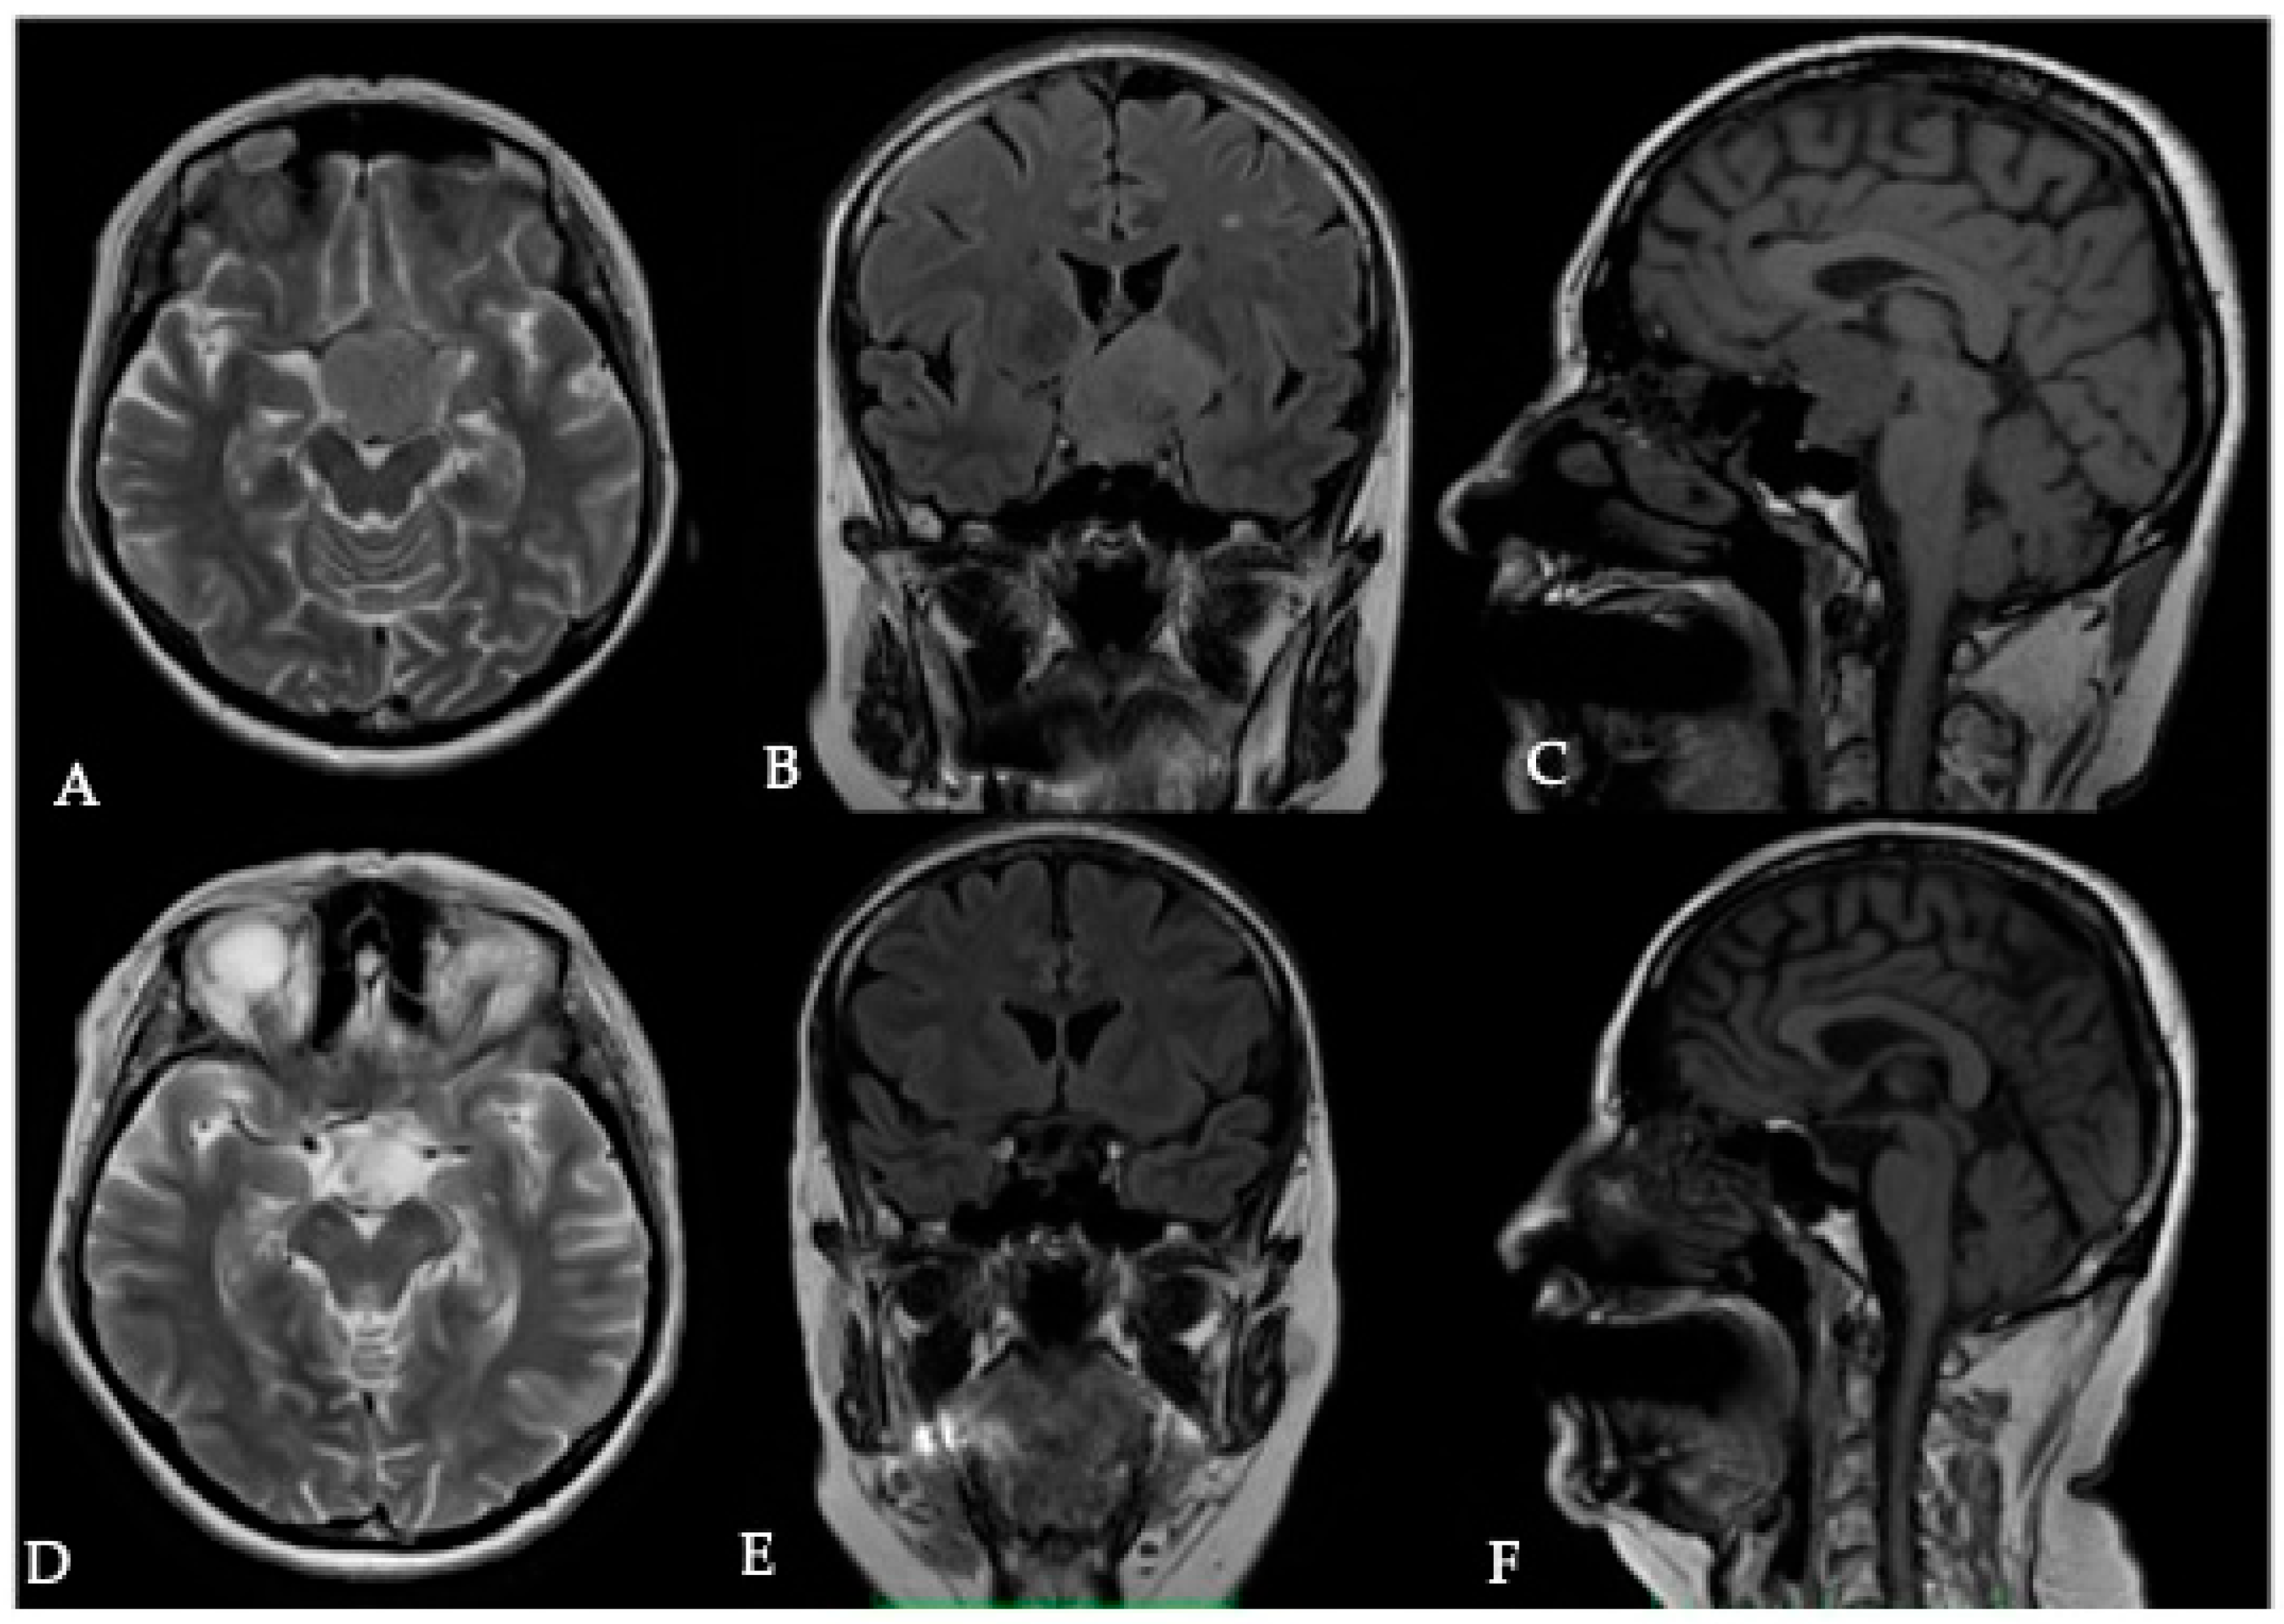

5. Assessment of Peritumoral Brain Edema (PTBE)

5.1. Surgical Significance

5.2. Imaging Evaluation

5.3. Key Surgical Considerations